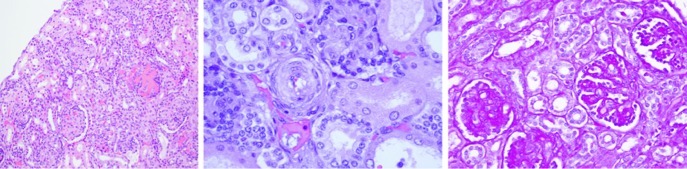

After the autopsy, the pathological findings in the kidneys showed poor cortical-medullary differentiation, and the glomeruli and arterioles were affected histologically. The glomerular component showed thickened capillary walls with endothelial cell swelling and other glomeruli in which the dilatation of the capillaries was prominent. Some areas of mesangiolysis were also observed. The vascular changes affected the intraglomerular arterioles with marked myointimal proliferation and narrowing of the vascular lumen (Fig. 2). In the central nervous system, haemorrhaging affected the putamen and the thalamus; we observed diffuse white matter involvement with spongiosis and necrosis, and severe astrocytosis. Microangiopathy was also observed with increased vessel wall thickness, reduced arterial inner diameter and capillary oedema. In the cerebellum, areas of necrosis and haemorrhage were detected: abnormalities in the cerebellar peduncles, the tegmentum and the bulbar olive were seen (Fig. 3).

Fig. 2.

The histopathological findings in the patient kidney. Microangiopathy was observed with thickened vessel walls and a reduction of the arterial inner diameter and capillary oedema. Left panel: glomeruli with thickening of the capillary walls and glomeruli with prominent capillary dilatation (×100). Middle panel: marked myointimal proliferation with narrowing of the lumen (×400) observed with haematoxylin-eosin staining. Right panel: PAS staining (×200) disclosed glomerular mesangiolysis

Fig. 3.

The histopathological findings show microangiopathy in different areas of central nervous system. Upper left panel: cerebellar peduncles with myointimal proliferation of vessels. Upper right panel: vessel myointimal proliferation in the hippocampus. Lower panels: microhaemorrhage with a high content of macrophages containing hemosiderin, microglia activation (left) and recent bleeding in the cerebellum (right)